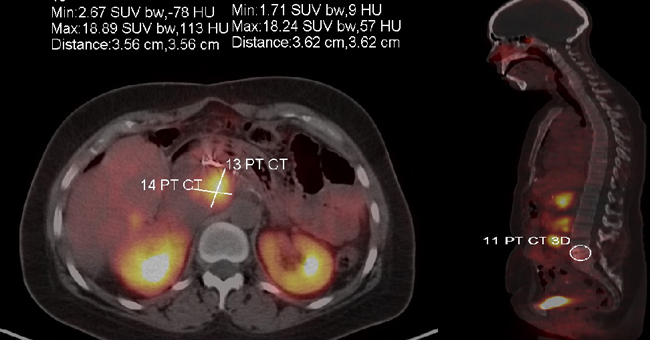

A 43-year-old female was in her usual state of health until about January of 2011 when she developed nausea, vomiting and diarrhea. Diarrhea persisted for a couple of months and she sought medical help in March 2011. Initial conservative management followed by a detailed workup done by a gastroenterologist was negative. Later, in August 2011 the patient presented to ED with complaints of melena. Her CT scan revealed a 9-cm mass in the tail of her pancreas with hepatic metastasis. Liver biopsy confirmed grade 2 neuroendocrine tumor (Ki-67 of 6%). The patient was initiated on Sandostatin LAR 30 mg every 30 days. She noticed rapid improvement in her energy level. She subsequently underwent Y90 radio-embolism of hepatic metastatic disease first in the right lobe of the liver followed by the left lobe in the months of September and October 2011. The patient had a stable course until December 2011, she had another episode of GI bleed. In January 2012 she underwent partial pancreatectomy, splenectomy, partial gastrectomy and left hepatic lobectomy. She was started on sunitinib in February 2012, which she had to rapidly discontinue within a month due to severe fatigue. She was started on capecitabine and temozolomide (CAPTEM) in April 2012. The patient tolerated CAPTEM well and started gaining weight. An abdominal MRI from May 2013 showed mild worsening of some of the hepatic lesions, however the rest of the disease was stable. She underwent two more doses of Y-90 radioembolism. She was continued on long acting somatostatin analog and CAPTEM and her subsequent surveillance scan in November 2013 showed stable disease. A follow-up MRI of the abdomen in February 2014 showed mild progression of one of the hepatic lesions. She was taken off CAPTEM and started on everolimus 10 mg daily. We had to reduce the dose of everolimus to 7.5 mg daily due to stomatitis. The patient did exceptionally well on the reduced dose of everolimus and had stable disease until October 2015, at which time she was enrolled into a Phase I clinical trial of fosbretabulin for progressive disease in the liver and retroperitoneum. The patient got the first dose of fosbretabulin in November 2015. She only received three cycles of fosbretabulin before she developed disease progression in the left supraclavicular and left axillary lymph nodes. In February 2016 she was started on off-label pembrolizumab. She had stable disease on pembrolizumab for 16 months before her disease progressed in axilla and breast. Figure 3 shows the current disease burden of patient with help of gallium DOTATATE scan.

Figure 3: Gallium DOTATATE scan sowing disease burden at the time of progression on immune checkpoint inhibitor therapy (case 1)